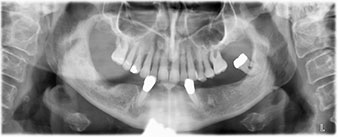

Пациентката е 64-годишна жена с частично обеззъбяване на зъби 38, 33 и 43 и частична долночелюстна протеза (Фиг. 1 и 2).

частично обеззъбяване

Фиг. 1

Фиг. 2